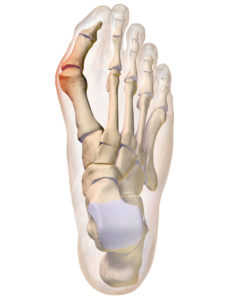

L’alluce valgo è una deformazione della parte anteriore del piede, conseguenza di una deviazione dell’alluce verso le altre dita del piede. Questo spostamento causa un tipico rigonfiamento laterale a livello della testa del primo metatarso. L’angolo tra il metatarso dell’alluce e quello del secondo dito si modifica progressivamente, con spostamento della base dell’alluce verso l’esterno. Questa deformità ossea è di solito associata a un’infiammazione costante o recidivante della borsa mucosa che si trova alla base dell’impianto dell’alluce stesso. Il sintomo principale dell’alluce valgo consiste nella presenza di dolore, che riflette un cambiamento nell’anatomia del piede. La deviazione laterale dell’alluce evidenzia la formazione della cosiddetta “cipolla“, una protuberanza che indica un’infiammazione molto dolorosa (borsite). Se l’alluce valgo viene trascurato, tende a peggiorare in maniera progressiva: il disturbo inizia con l’alluce rivolto verso il secondo dito, fino a determinare cambiamenti nell’allineamento effettivo delle ossa del piede. Nel corso degli anni, infatti, si possono instaurare anche deformità delle altre dita e forti dolori al piede (metatarsalgie).

Lo schema mostra che l’alluce è deviato lateralmente (valgo). Colpisce maggiormente la “cipolla” costituita dalla sporgenza sotto la pelle della testa del 1° metatarsale; urta contro la scarpa e causa infiammazione e dolore.

- 1. ALLUCE VALGO = spostamento laterale dell’alluce;

- 2. METATARSO VARO = spostamento verso l’interno del 1° metatarso.

Nella foto si vede un alluce valgo deformato (ROSSO) e un alluce operato tre anni fa con la tecnica del dott. Scala (VERDE). L’immagine mostra l’allineamento delle ossa del piede. L’alluce è bello dritto e non si sposta più.